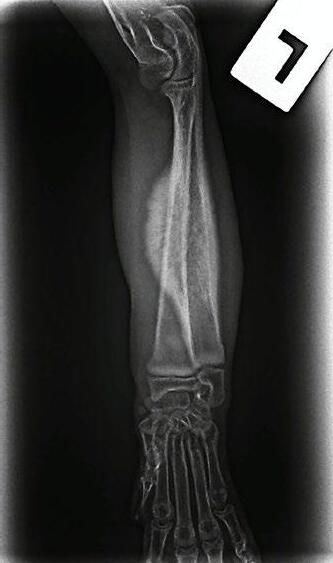

Hotch was booked in for routine castration 4 weeks later with repeat radiographs taken, which already showed improvement (see images). He continued with only oral clindamycin for a further 4 months with regular weight checkups, and dose adjustments as required. We did repeat radiographs under mild sedation a further 2 times to ensure the bone was remodeling as expected (Figure 3 ). Hotch responded almost immediately to the antibiotics and never showed signs of lameness or pain again. He was a robust, busy kitten.

Figure 3. Radiograph of the affected leg showing resolving infection and remodeling of the lesion back into a more normal skeletal appearance

Figure 4. Final radiographs showing near normal appearance of the lesion (A & B) after extensive remodelling during growth. C is the contralateral normal limb for purposes of comparison.